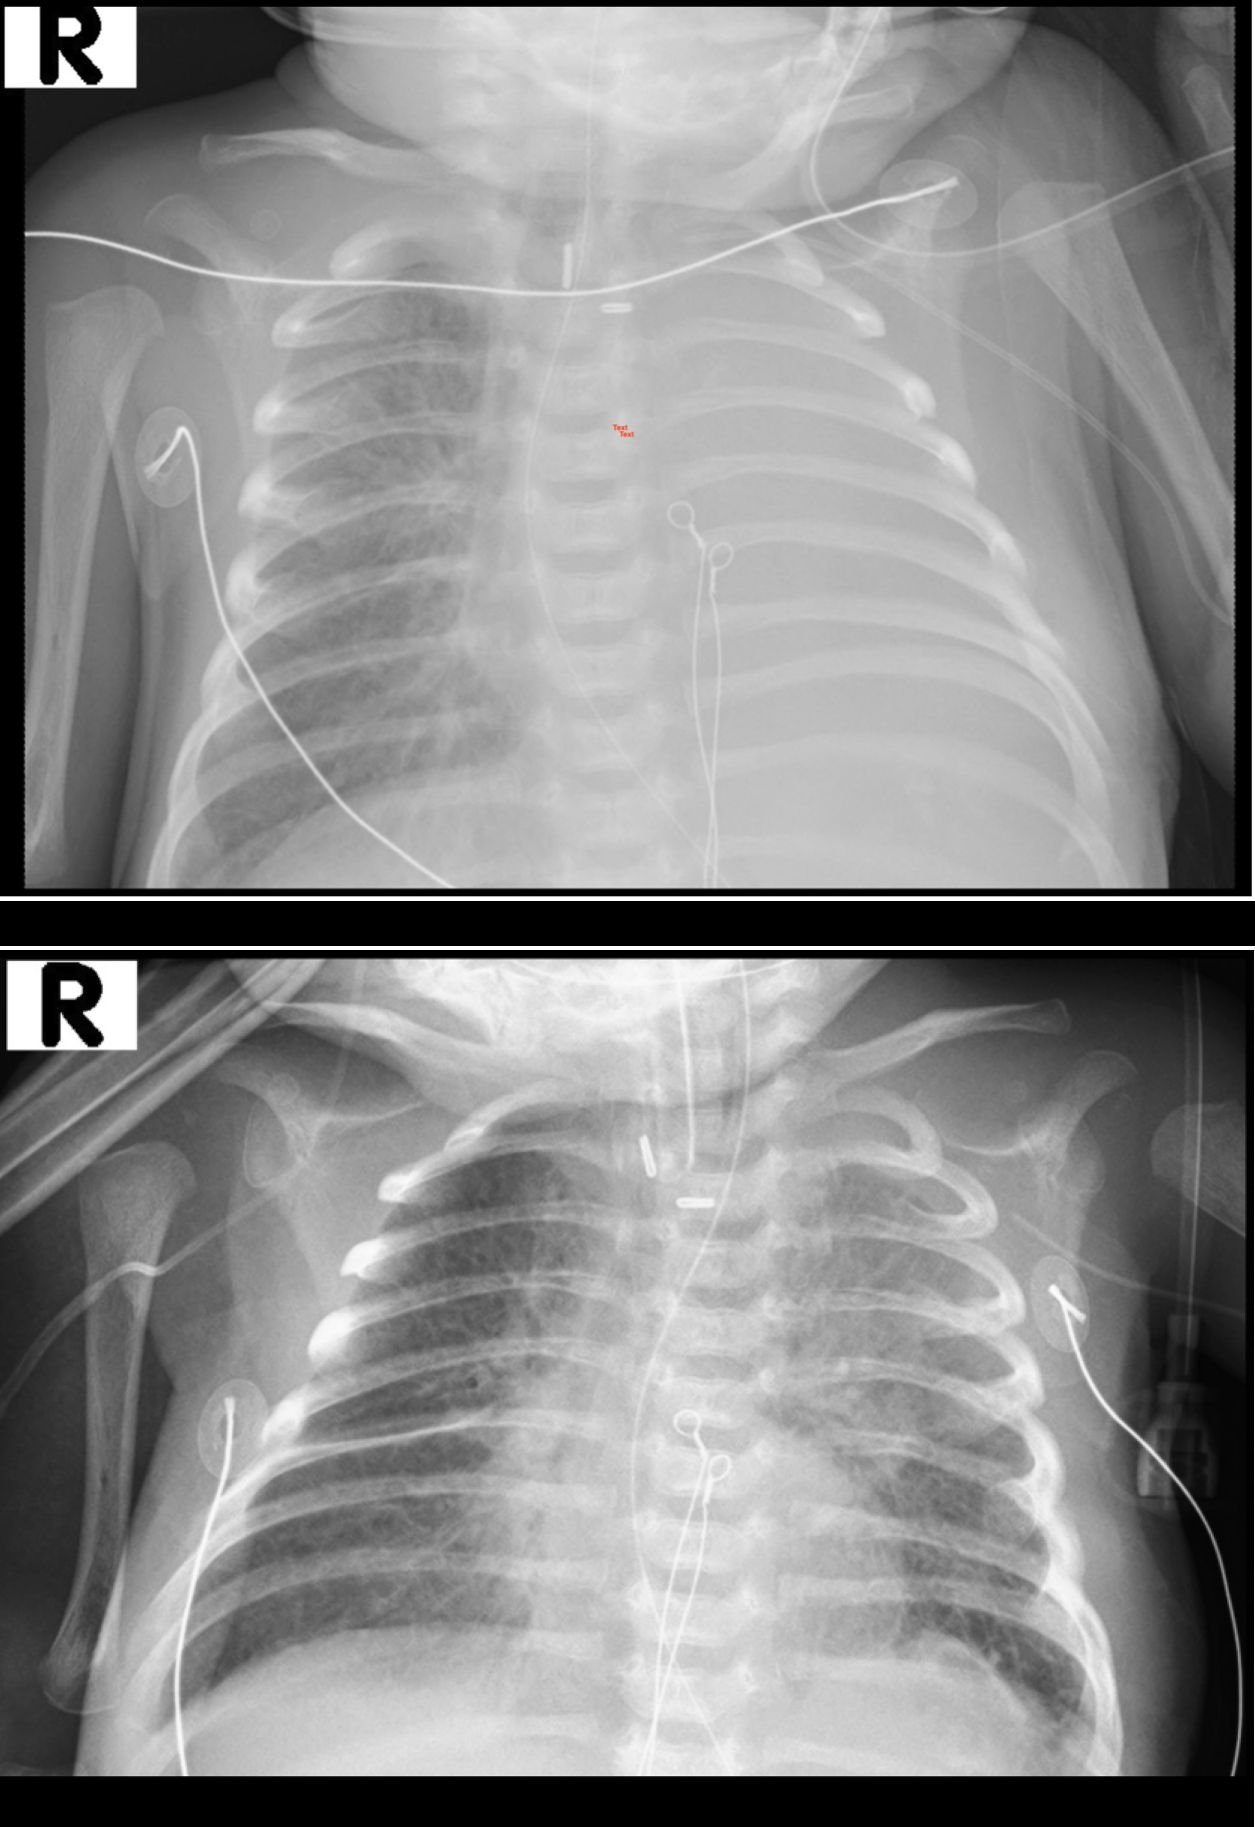

Results: After three insufflation cycles to 30 cm H2O and surfactant administration in two aliquots, elective intubation was maintained for 24 hours to preserve lung recruitment. Post-procedure, the left lung was re-aerated with no evidence of pneumothorax.